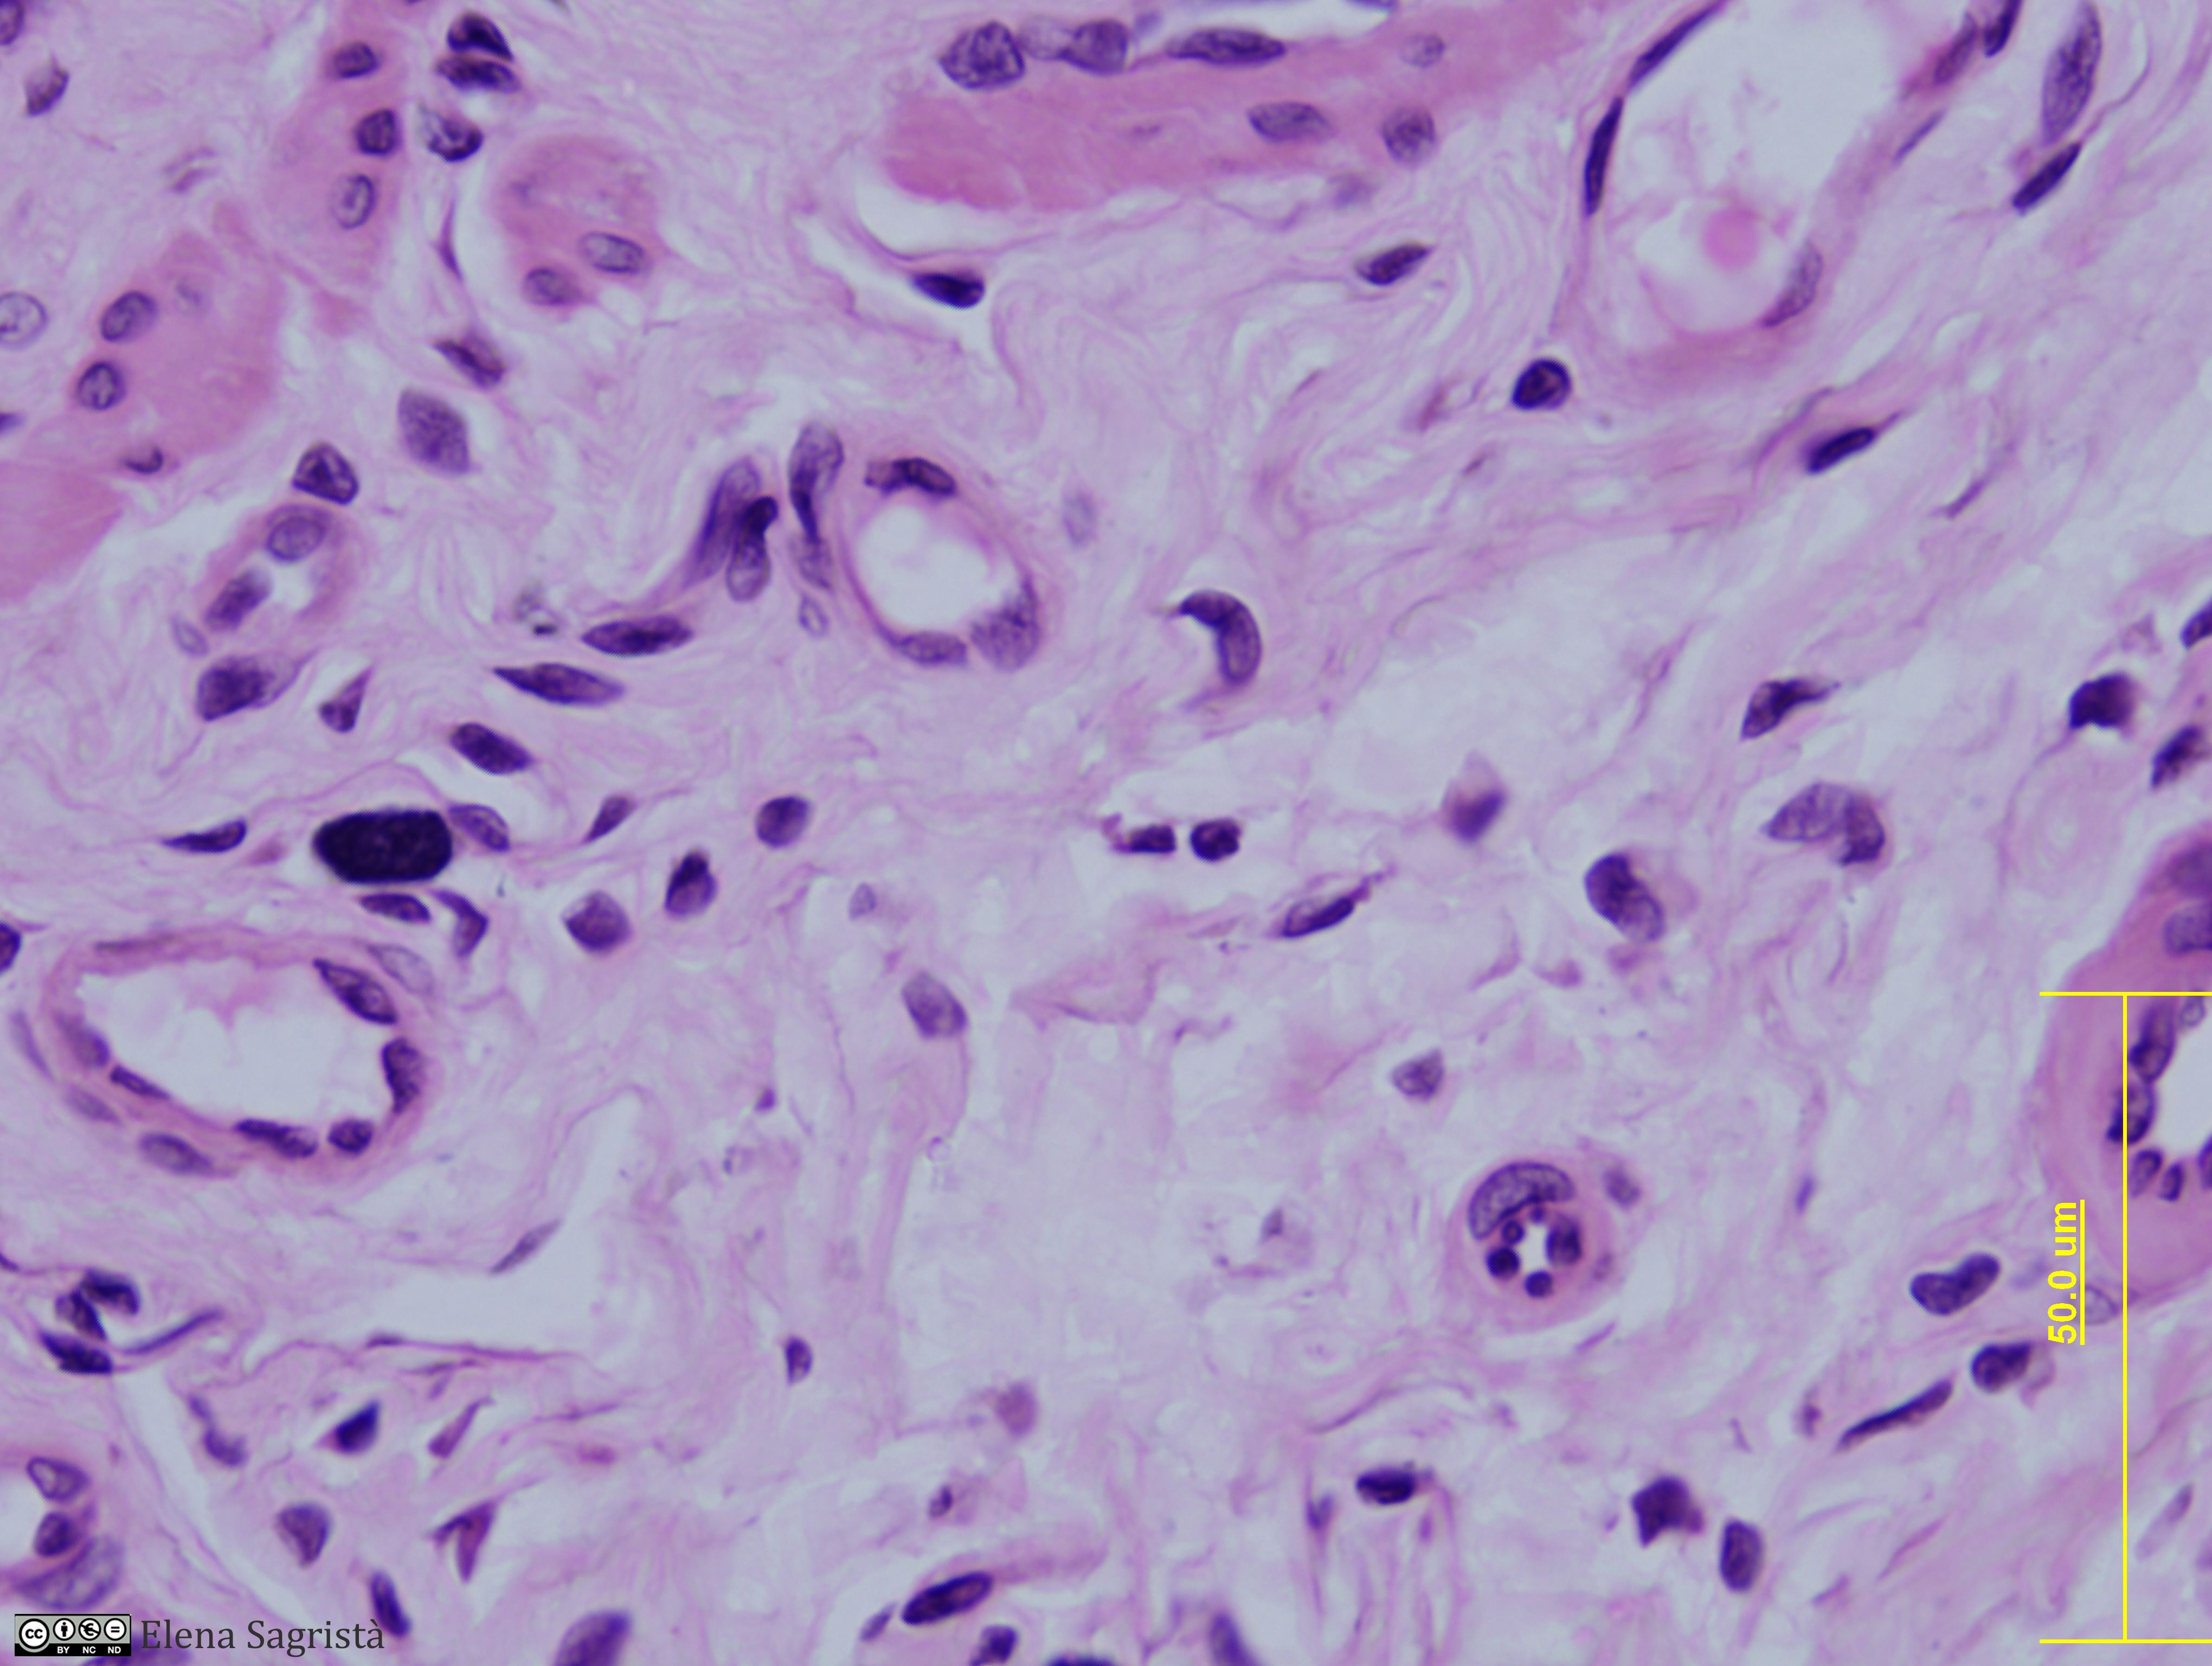

Histologia imatges: 02 Teixit conjuntiu

Imatges de preparacions histològiques de Teixit conjuntiu. Microscopia òptica.